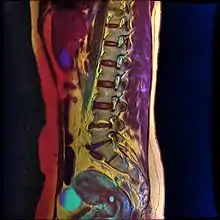

Color MRI showing nabothian cyst as small blue circle in cervical region.

Nabothian cysts are also incidentally found during MRI imaging. During the healing process of chronic cervicitis, squamous epithelium of ectocervix proliferates and enter the cervical canal (endocervix), covering and obstructing the columnar epithelium of endocervical glands. Thus, retention of mucus in the endocervical glands causes cyst formation. The size of the cyst may vary from a few millimetres to 4 cm in diameter.[3]

If a cyst has an unusual appearance, a colposcopy will be performed to rule out other diagnoses.[4] If the blood vessels are short, comma-like or corkscrew-shaped and bleed on contact, then the cyst may be a very rare mucin-producing carcinoma of the cervix.[4] Magnetic resonance imaging is used to distinguish cancer from the typical nabothian cyst.[4]

T1-weighted MRI imaging would show intermediate to high intensity while T2-weighted imaging would show high signal intensity. Findings of solid components separating multiple cysts would be suggestive of adenoma malignum (a form of cervical cancer).[3]